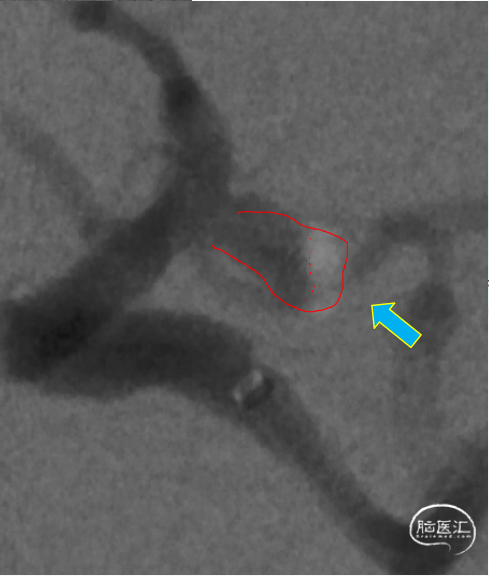

造影确认工作位,瘤内可见造影剂滞留。

工作角度造影

右侧颈内动脉正位造影

右侧颈内动脉侧位造影